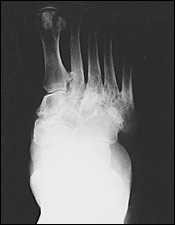

病人在癒合期時coalescence stage (subacute Charcot)表現骨頭碎片的再吸收,在修補,再強化期(chronic Charcot)則表現骨頭碎片的融合,如圖3。

FIGURE 3. Consolidation, or reparative, stage (chronic Charcot).

最後導致一個穩定但卻變型的腳,如圖4。

圖4. Rocker-bottom foot deformity secondary to Charcot process.腳底如同搖椅的底部般,是凸的。